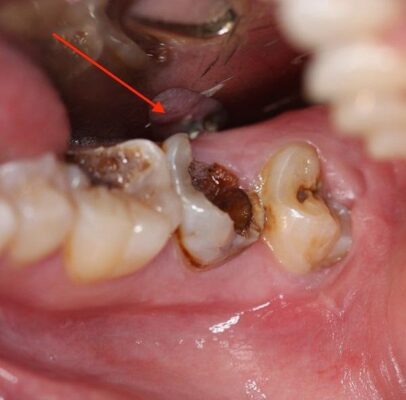

- Vết đen bám trên rãnh răng, bề mặt nhai làm răng bị sâu đen.

- Răng bị ê buốt khi nhai khi ăn đồ ngọt, đồ cay nóng, đồ lạnh.